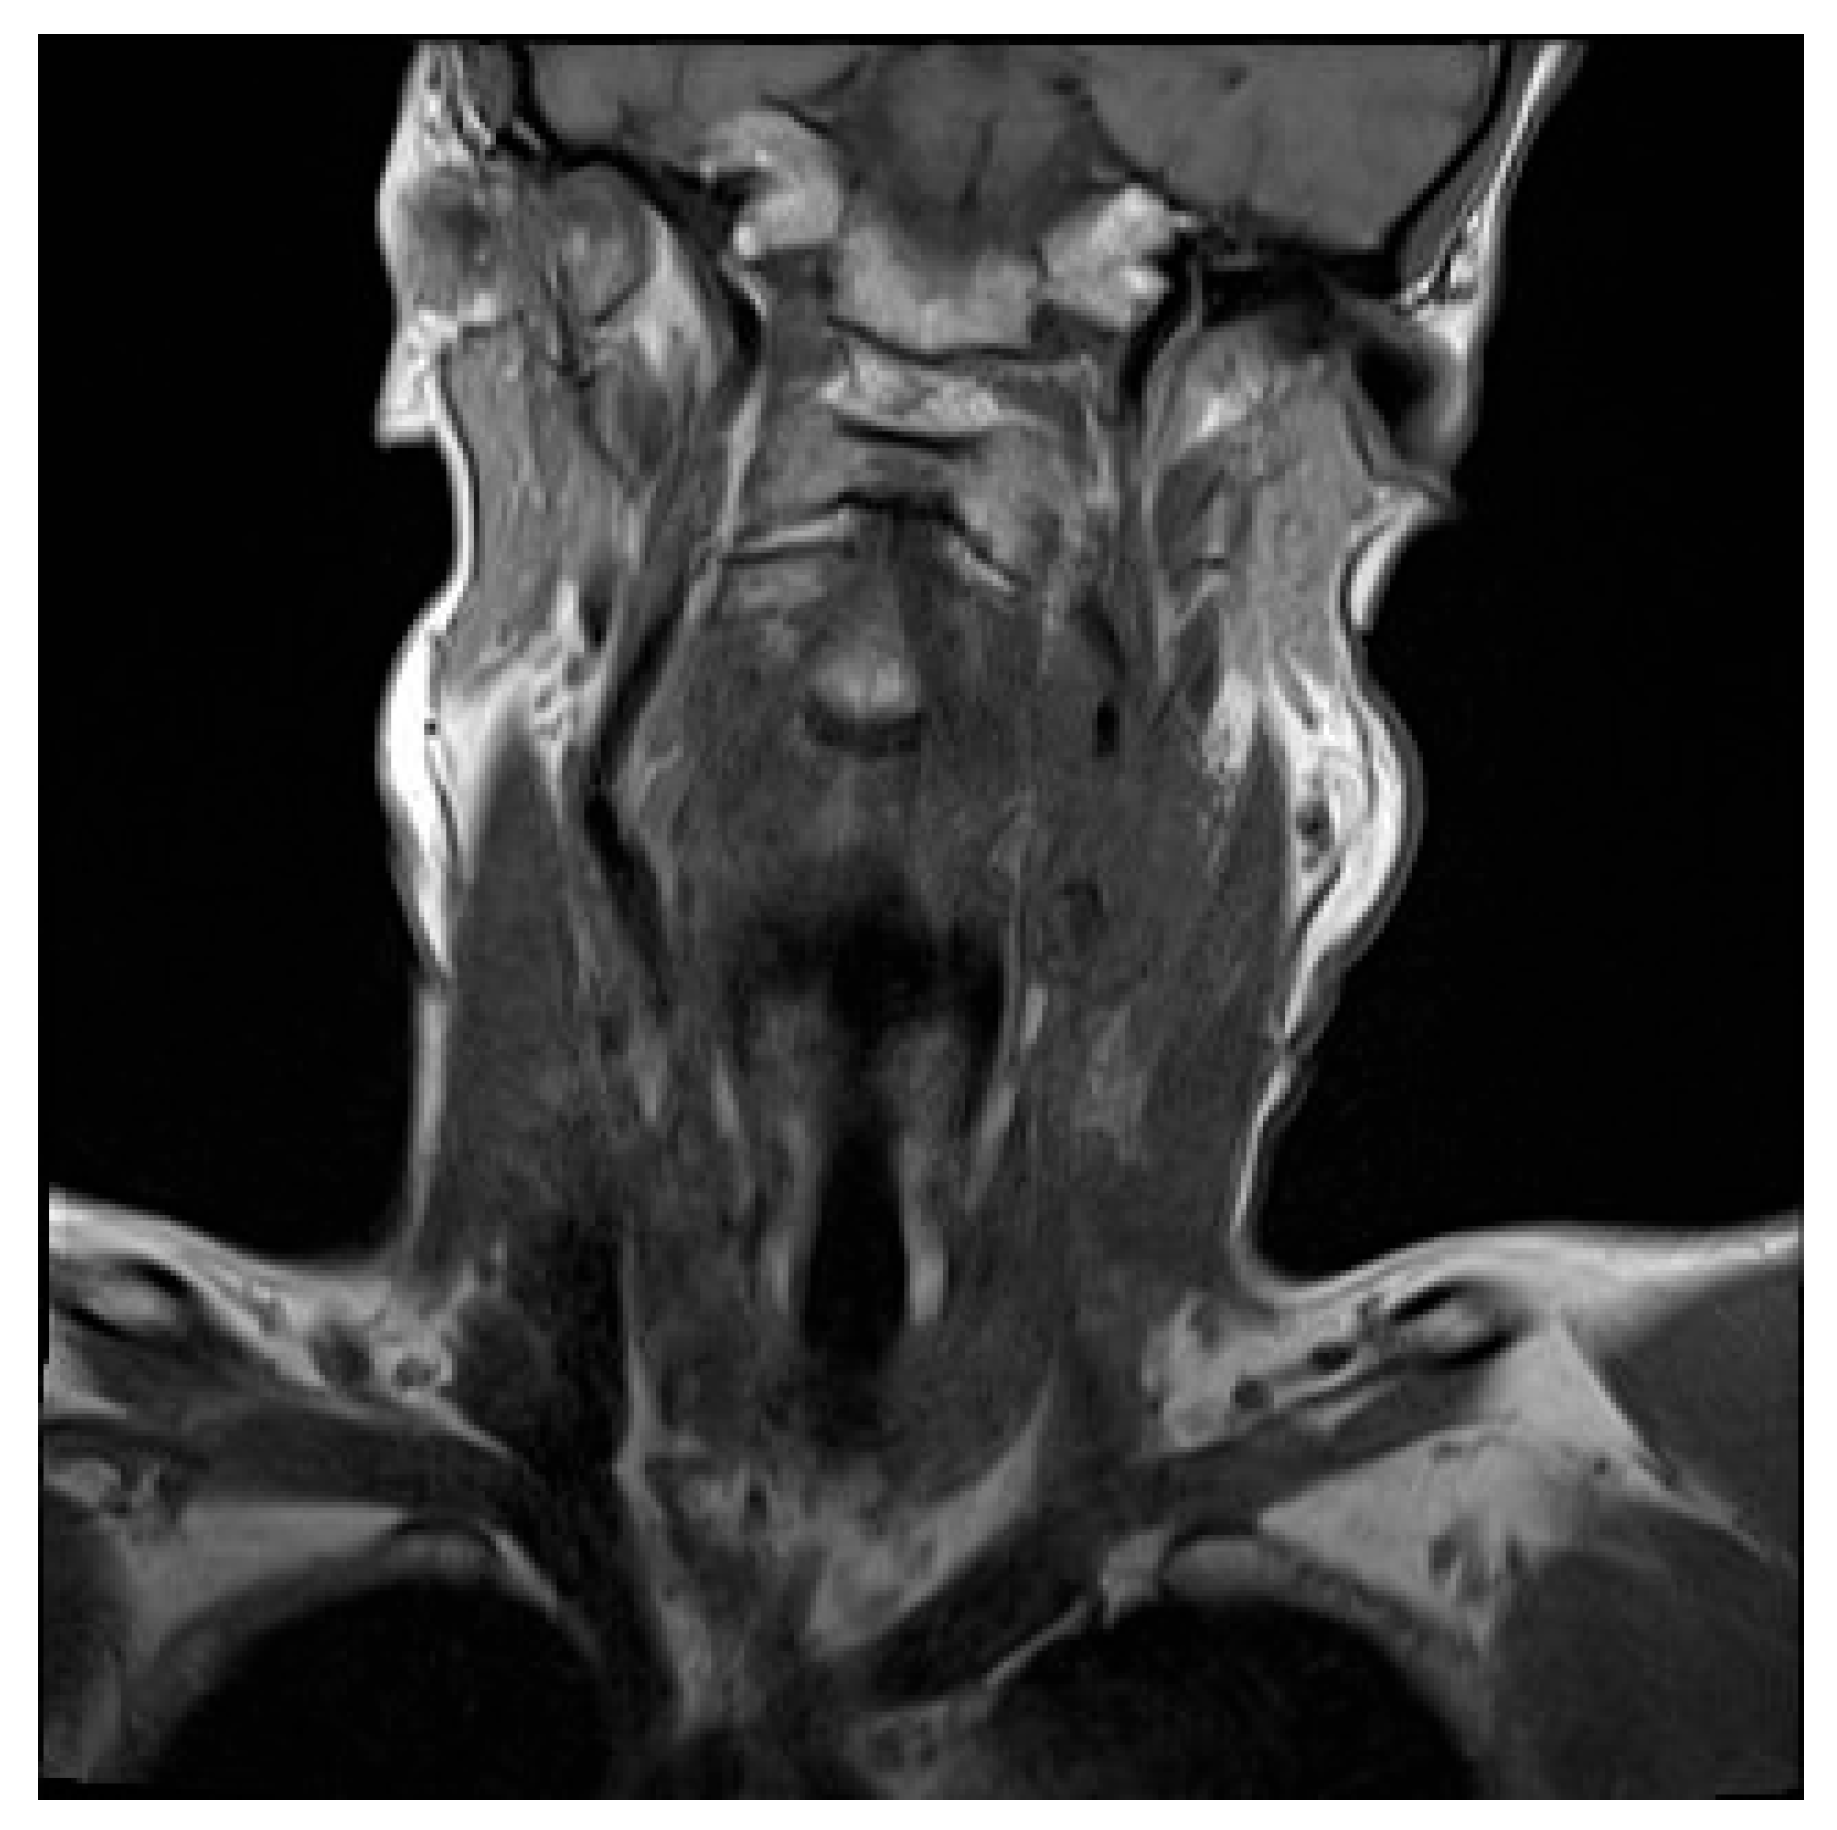

Initial contrast-enhanced CT neck revealed a large left-sided neck mass, measuring 3.5 by 4.6cm. Further characterisation by contrast-enhanced MRI showed the neck mass to be encasing the upper common carotid artery, the carotid bulb and the internal carotid artery on the left side. This mass was also compressing the left internal jugular vein, occluding it and resulting in thrombosis (Figure 1).

Figure 1. MRI – Mass encasing the left common carotid, carotid bulb and internal carotid arteries. Left-sided compressive internal jugular thrombosis.